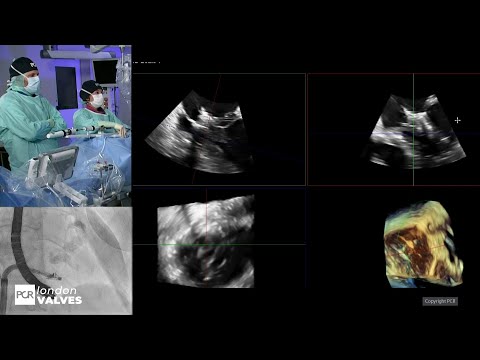

Advancing structural heart with 3D ICE and device guidance - PCR London Valves 2025

Cracking the tricuspid code "the Bicaval revolution" - PCR London Valves 2025

Innovation and imaging guidance in tricuspid valve replacement - PCR London Valves 2021